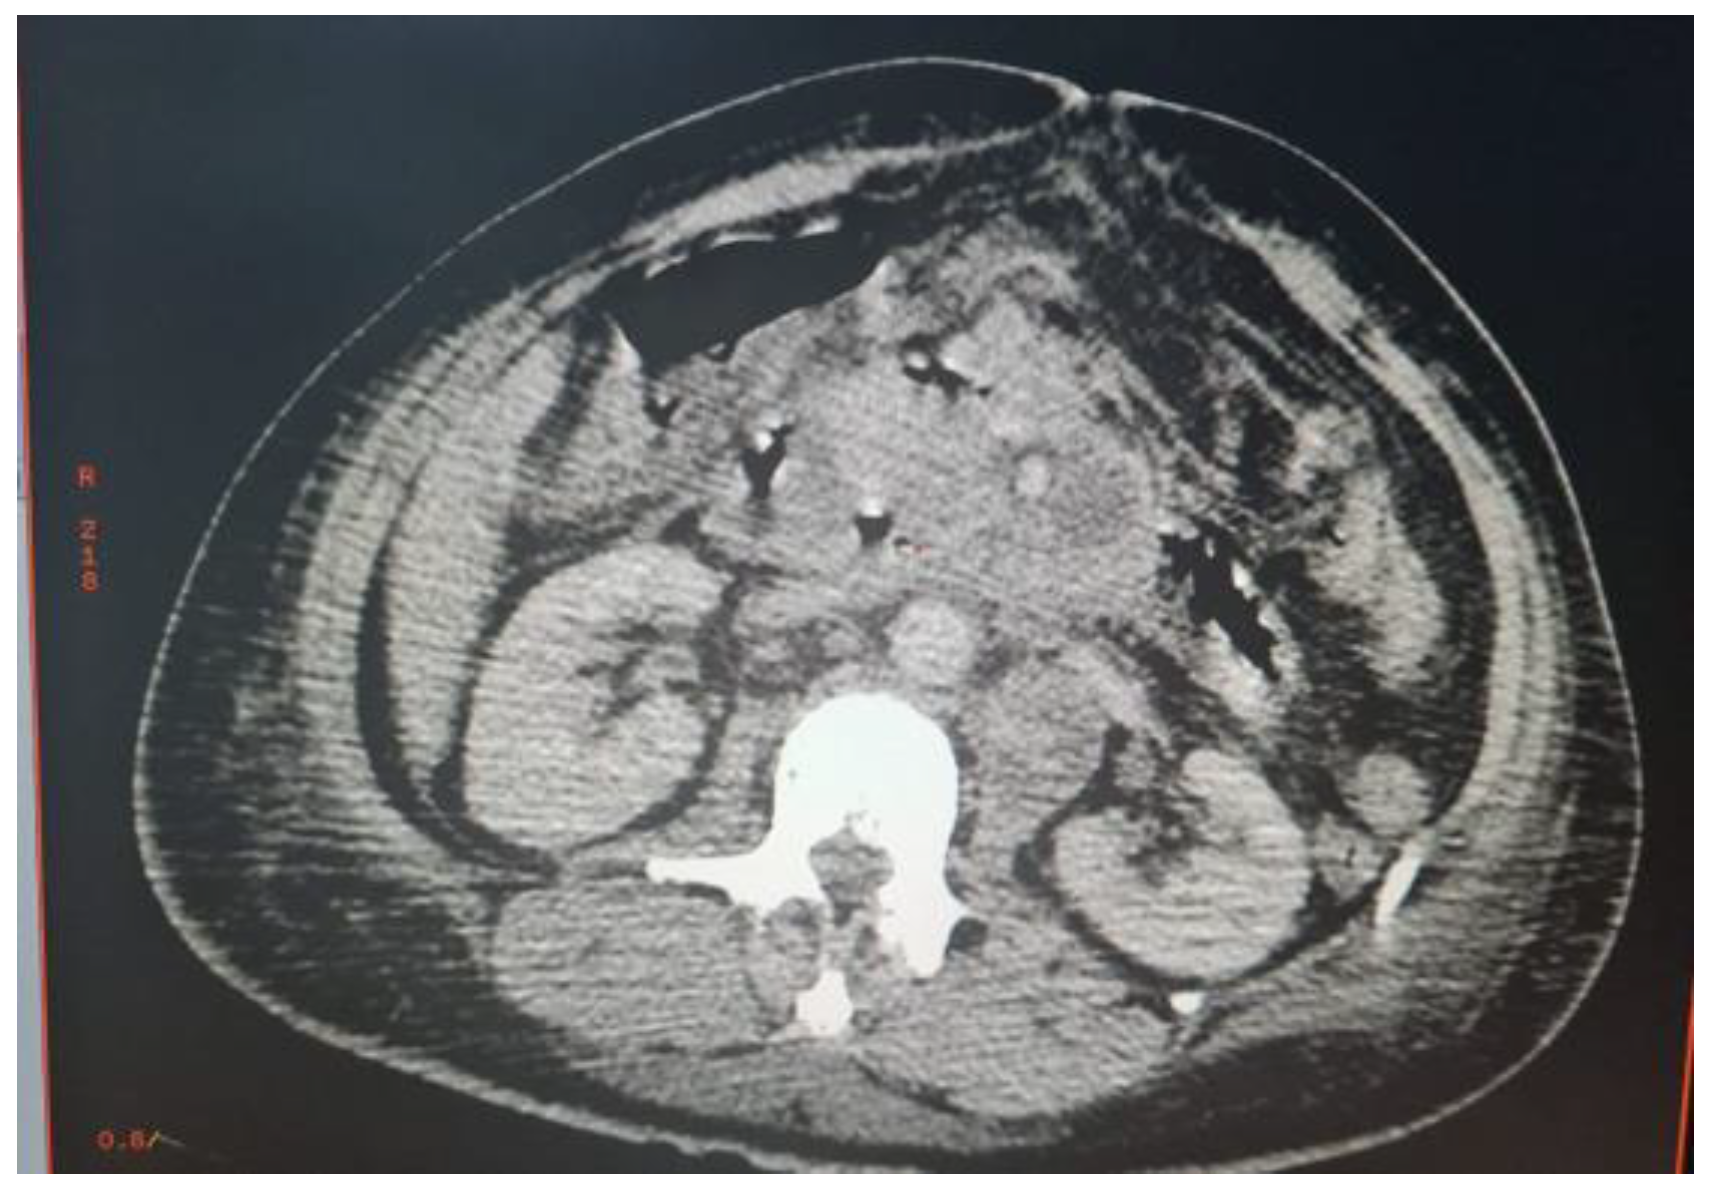

Abdominal CT scan showed a bulbar perforation and multiple deep necrotic adenopathies of infectious or tumoral origin. An exploratory laparotomy was decided (Figure 1).

Figure 1. Multiple deep necrotic intra and retroperitoneal adenopathies.